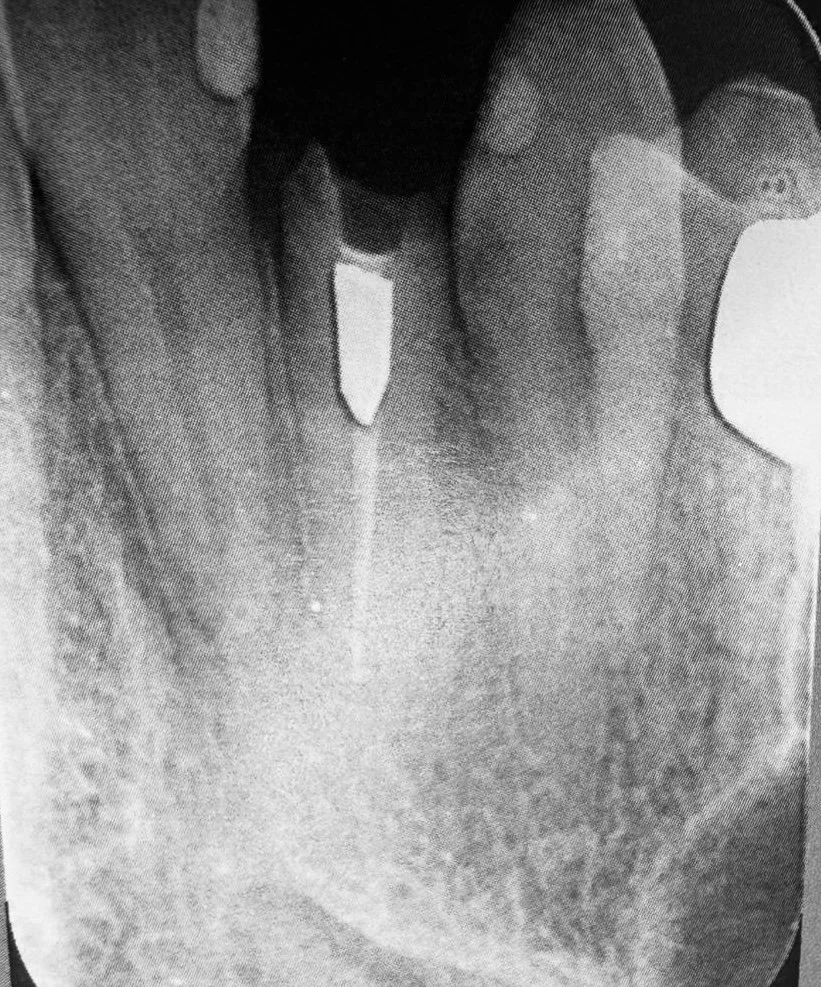

Estrazione e Implantologia a Carico Immediato

Riabilitazione post estrazione con impianto